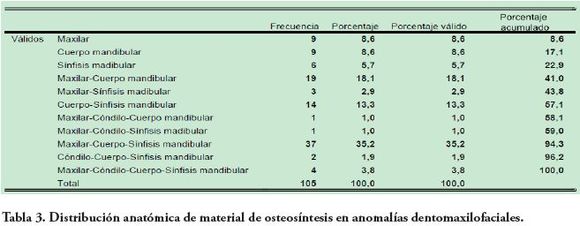

Con impresión diagnóstica de anomalía dentofacial (fig. 3), 30 fueron hombres (28,5 %) y 75 mujeres (71,4 %) (p=0,0002) con un OR de 3,36 para las mujeres. La mayor corrección quirúrgica de anomalías dentofaciales se presentó en el grupo de edades de 21 y 30 años con 40 pacientes (53,3 %) y la de menor fue entre 61 y 70 años con 1 paciente (1,3 %) y 50 radiografías (47,6 %) presentaban ortodoncia. Se identificaron 8 radiografías (7,6 %) con anclajes condilares y el 58 % de las radiografías presentaron evidencia de cirugía bimaxilar. La distribución de la ubicación anatómica del material de osteosíntesis en hallazgos de ADF se presenta en la Tabla 3.